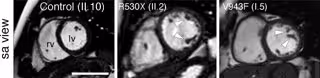

Imágenes de resonancia magnética cardíaca de un familiar sano (izquierda) y dos pacientes de cardiomiopatía no compactada (centro y derecha). Se pueden apreciar las trabéculas características de la enfermedad señaladas con puntas de flecha.

Imágenes de resonancia magnética cardíaca de un familiar sano (izquierda) y dos pacientes de cardiomiopatía no compactada (centro y derecha). Se pueden apreciar las trabéculas características de la enfermedad señaladas con puntas de flecha. - CNIC